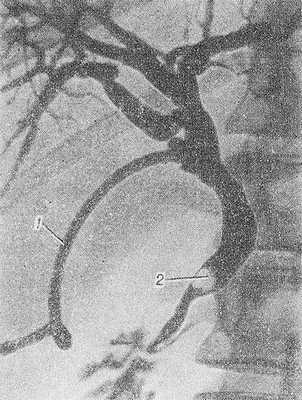

Рис. 2. Интраоперационная холангиография при желчнокаменной болезни (прямая проекция): общий желчный проток (1) расширен, в его дистальной части группа камней (2), контрастное вещество выходит в двенадцатиперстную кишку (3); в общем желчном протоке виден катетер.

Интраоперационная холангиография предложена Мирисси (P.L. Mirizzi) в 1931 году. Ее выполняют на операционном столе после вскрытия брюшной полости. Проведение интраоперационной холангиографии требует четкого взаимодействия хирурга и рентгенолога. Показания к этому виду холангиографии те же, что и к хирургическому исследованию желчных протоков. Абсолютных противопоказаний нет, а относительными являются острый холангит и тяжелое состояние больного, при котором мероприятия ограничиваются операцией отведения гноя и желчи. Интраоперационная холангиография позволяет выяснить состояние желчных протоков и избежать холедохотомии (см.) примерно у половины больных, которым производят операции на желчных путях. Интраоперационную холангиографию выполняют в операционной, оборудованной рентгеновской установкой с трехфазным генератором; рентгенотелевизионное исследование и видео-магнитную запись сочетают с обзорной рентгенографией. Холангиографию рекомендуется производить до инструментального исследования желчных протоков. Применяют разведенные (30—50%) растворы рентгеноконтрастных веществ, чтобы в интенсивной тени протоков были видны даже мелкие камни (рис. 2). Рентгеноконтрастное вещество вводят преимущественно через пузырный проток или непосредственно в общий желчный проток, вначале 5 —8 мл при невысоком давлении и выполняют первый снимок, а затем 10—15 мл под давлением, после чего производят второй снимок. При правильно проведенном исследовании осложнений не наблюдается.